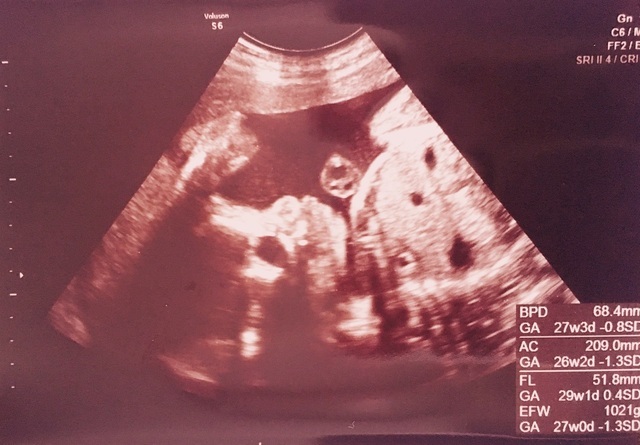

28週0日(28w0d)のエコー写真

28週0日(28w0d・女の子)|しおぽん さん(21歳)

エコー写真撮影時のエピソード:

初めて4Dエコーをみてとても感動しました。見た第一印象は鼻が低いなあって思いました(笑)でも、すごくかわいくてますます早く会いたくなりました。

あと、予定日まで1ヶ月きっていて正産期に入ってるので不安ですが頑張りたいです。